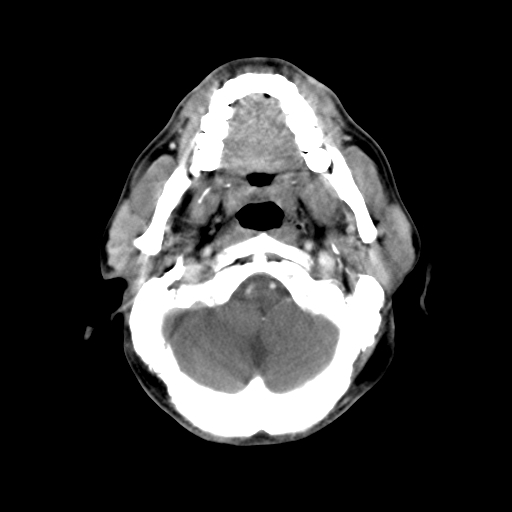

标题: CT24019:男,45岁,发现颈部肿物5个月。 [打印本页]

男,45岁,发现颈部肿物5个月,彩超示:双侧颈部及下颌部软组织增厚。

考虑双侧颈项部良性对称性脂肪增多症。